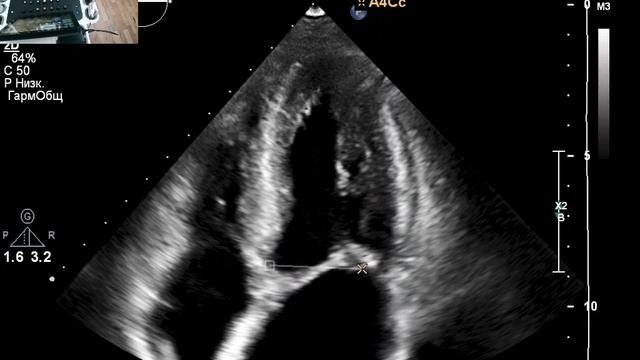

Ддлж по 1 типу по узи